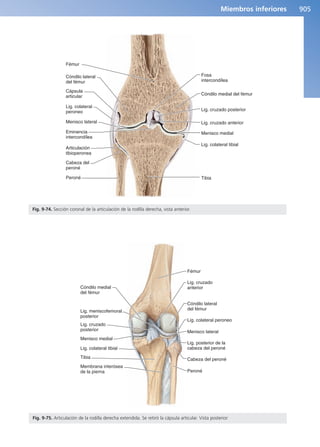

Complejo articular de la rodilla 904